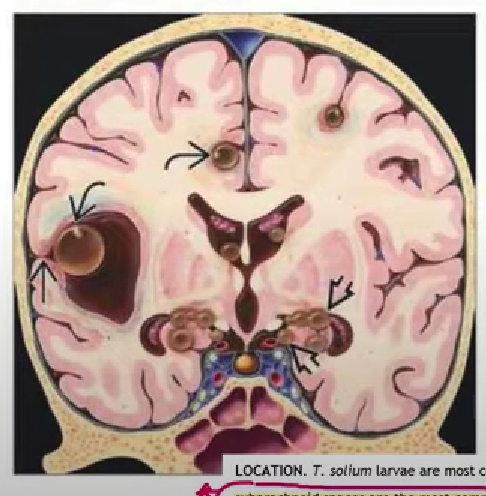

Common locations of Taenia Solium larvae in the brain/ neurocysticercosis.

Illustration from

Osborn's Brain